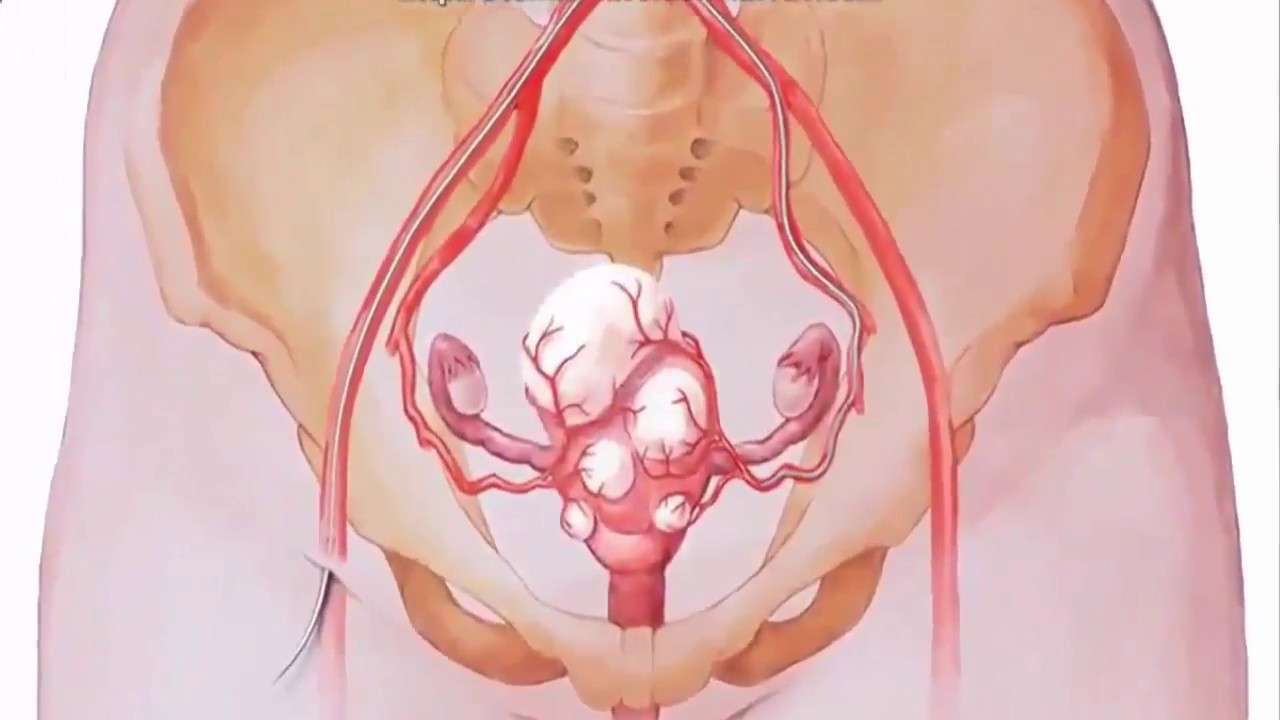

Анатомия женского организма: строение и функции матки

Раздел: Фотопуть к знанию